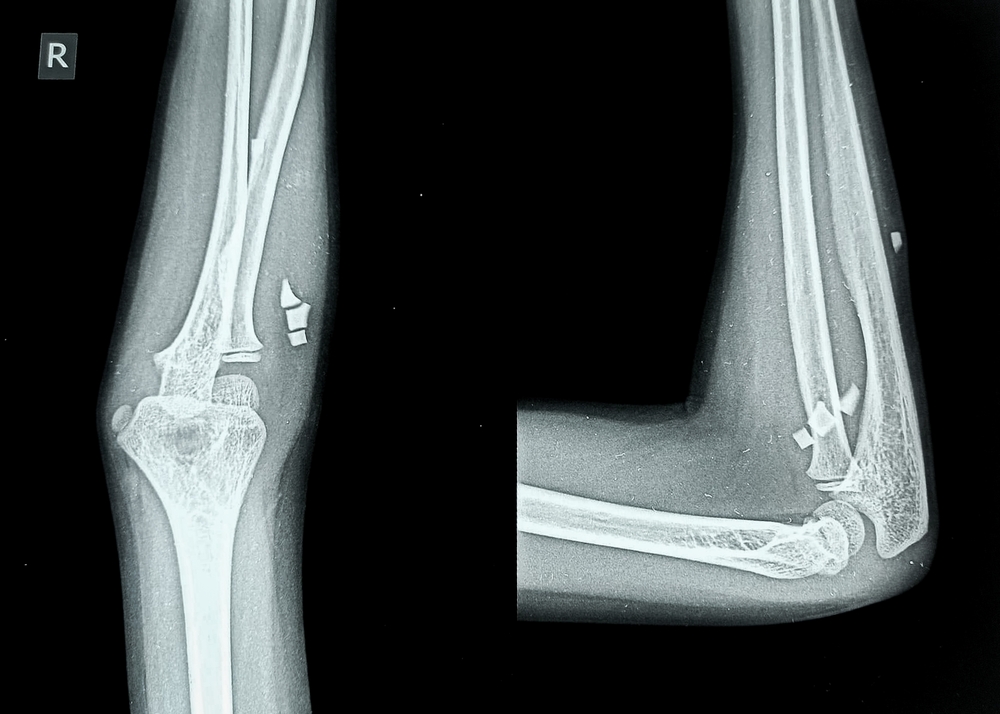

Рентген локтевого сустава (локтя) – это информативное и точное исследование, которое позволяет за короткое время установить патологию, локализованную в данной области. Этот метод является «золотым стандартом» в диагностике травматических и повреждений костей верхних конечностей. Пациент не испытывает в процессе проведения боли и неприятных ощущений, диагностика полностью неинвазивна. По результатам выдается подробное описание и серия снимков на цифровом носителе или в распечатке.

Рентген локтевого сустава – это доступный способ оценки состояния костей локтевого сустава. В процессе не требуется использования рентгеноконтрастного вещества, поскольку плотная костная ткань хорошо накапливает ионизирующее излучение. В нашей медицинской клинике используется современный аппарат с функцией Multi Tom Rax, что позволяет эффективно диагностировать дегенеративно-дистрофические изменения (артриты, артрозы, остеопорозы, ревматит), травматические повреждения (переломы, трещины, вывихи, подвывихи, смещения), новообразования (в том числе и опухоли), а также воспалительные процессы.

Для наиболее полной картины снимки выполняются в двух проекциях:

• Прямая проекция – предплечье плотно прижимается к диагностическому столу при разогнутом суставе. Данное положение дает максимальный обзор основных костей локтевого сустава;

• Боковая проекция – локоть согнут, а предплечье также прижато к диагностическому столу. Позволяет более точно визуализировать кости, затененные в первом варианте.

Особенное внимание уделяется врачом при описании снимков следующим моментам:

• Для боковой и прямой проекции не визуализируется патологических изменений мягких тканей – мышц, сухожилий и связок;

• Прослеживаются ровные контуры всех основных костей локтевого сустава, не визуализируется зон с повышенным накоплением излучения, нет новообразований и наростов;

• Зафиксирован нормальный уровень конгруэнтности костей, анатомическая форма и толщина суставных щелей не изменены.